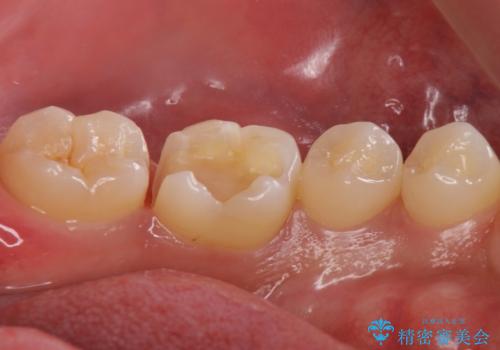

奥歯が欠けた セラミックインレーでの治療

- 奥歯が欠けたとのことで来院されました。

白い詰め物をご希望されたため、セラミックインレーでの治療を行います。

治療前後で比べると、詰め物と歯の間のすき間もなくなりセラミックインレーの適合の良さが伺えます。